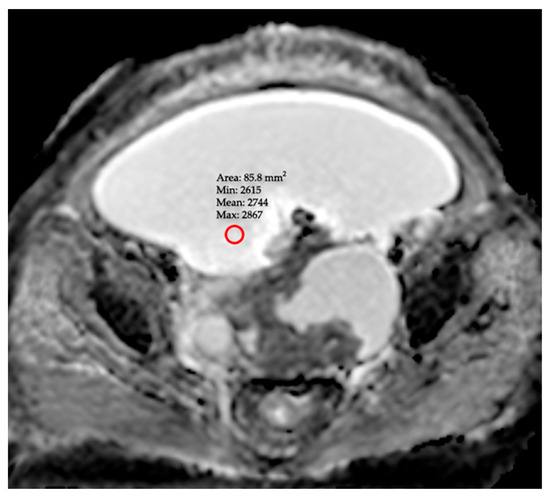

Background/Objectives: This study aimed to evaluate the diagnostic accuracy of Apparent Diffusion Coefficient (ADC) values, derived from Diffusion-Weighted Imaging (DWI), in differentiating benign and malignant ascites. Methods: This retrospective study included 150 patients (85 benign, 65 malignant) who underwent abdominal MRI. All patients were scanned on a DWI sequence (b-values: 0, 500, and 1000 s/mm2). Two experienced radiologists, blinded to clinical and cytological outcomes, measured the mean ADC (ADCmean) from three distinct ROIs and the minimum ADC (ADCmin) from the area of lowest signal intensity on the ADC map. The diagnostic performance of ADC parameters and the Serum-Ascites Albumin Gradient (SAAG) was assessed using Receiver Operating Characteristic (ROC) curve analysis. Results: The mean values of ADCmean (3162 ± 204 × 10−6 mm2/s) and ADCmin (2885 ± 148 × 10−6 mm2/s) in the malignant group were significantly lower than those in the benign group (3596 ± 239 and 3322 ± 218 × 10−6 mm2/s; p = 0.006 and p = 0.0016, respectively). Inter-observer agreement was good for both ADCmean (ICC = 0.844) and ADCmin (ICC = 0.879). In the ROC analysis, ADCmin demonstrated the highest diagnostic performance (AUC: 0.930). An optimal cut-off value for ADCmin of ≤ 2983 × 10−6 mm2/s yielded 81.5% sensitivity and 85.8% specificity. The diagnostic performance of ADCmin was found to be superior to that of ADCmean (AUC: 0.877) and SAAG (AUC: 0.919). Conclusions: ADC values derived from DWI, particularly ADCmin, represent a highly accurate, non-invasive, and reproducible biomarker for differentiating benign from malignant ascites. The identified ADCmin threshold provides quantitative parameter that can aid in patient triage, especially when cytology is inconclusive, potential surrogate for fluid characterization. Full article